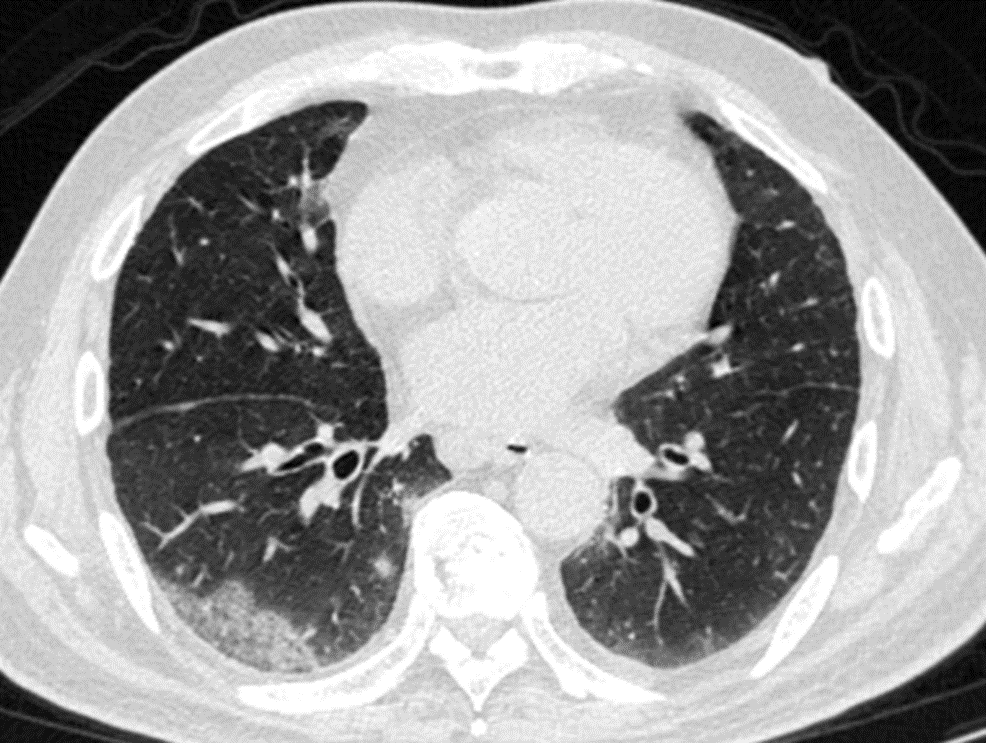

其实,这波omicron感染,确实肺炎比例比想象中要高,但很多都不会是大白肺,多数表现为双肺散发磨玻璃影,当然,也有单独的磨玻璃结节,特别容易表现为混合密度磨玻璃结节。其实很多新发的磨玻璃结节都是新冠肺炎,不用过于紧张,如果感染面积不大,一般临床上,也不需要特异性治疗,休息观察就行了。

CT提示,右肺下叶多发磨玻璃影。